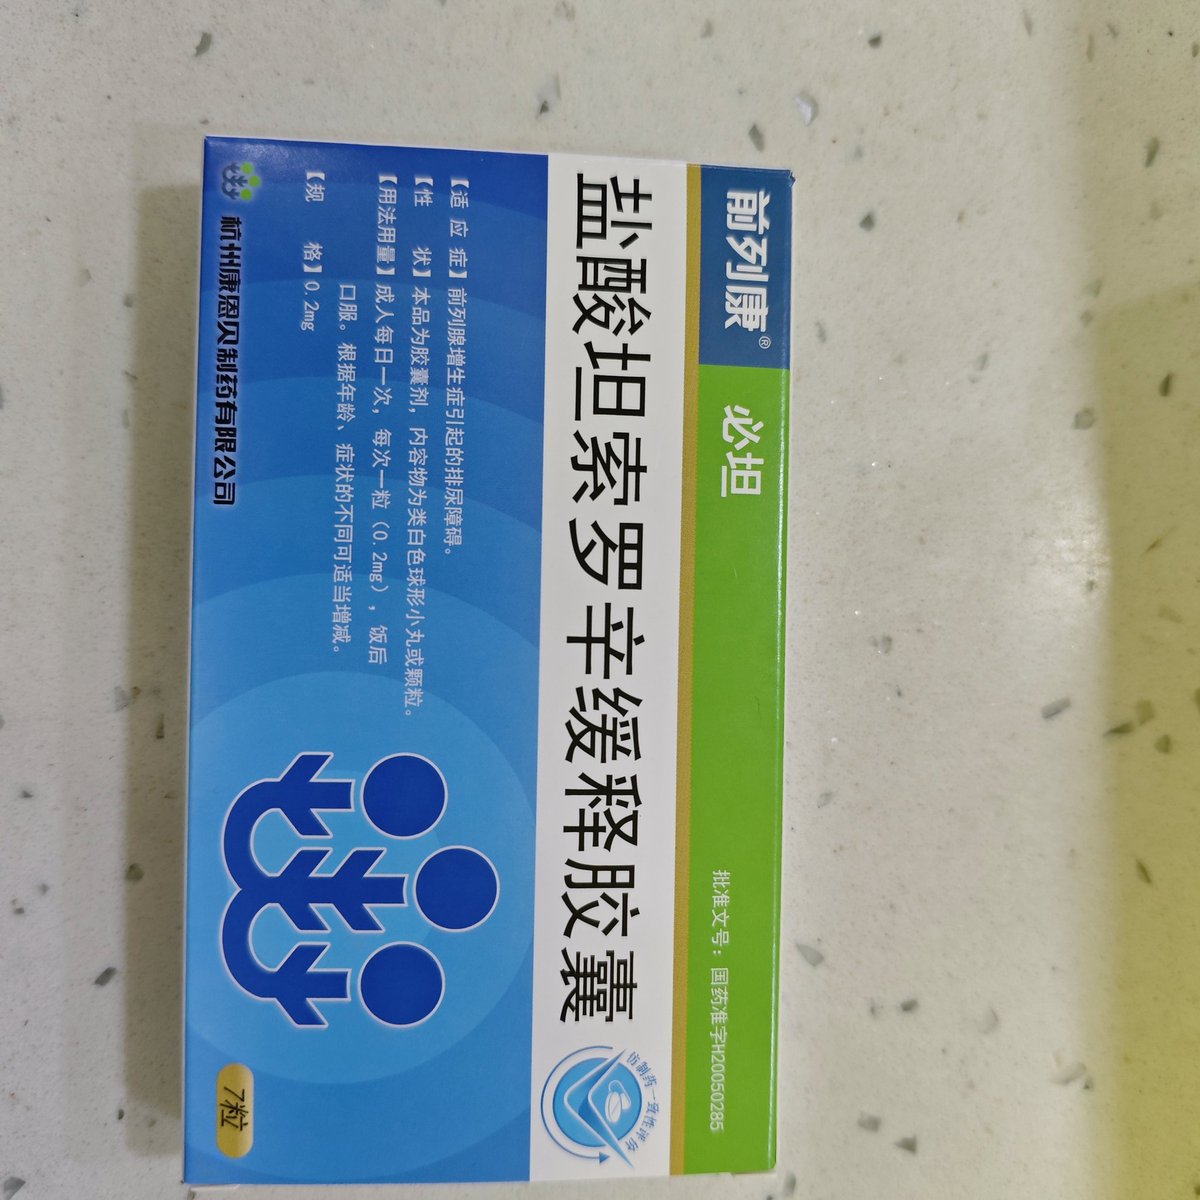

由于我现在快(痛经)痛死了,有感而发简单说说止痛药

常见NSAIDs先稍稍,首选塞来昔布,0.5-1h起效,对肠胃刺激小可以空腹服用,有中上的镇痛强度和中短的持续时间

那么有没有更强的呢🥹有,依托考昔,起效要1h以后,有着22h的长半衰期所以管一整天没什么问题,同样对胃刺激小适合我这种快痛晕过去了直接抓来吃

双氯芬酸钾起效也快适合空腹,但如果胃没那么好就可以一整个分不清哪里在痛了,所以还是垫点食物会比较好

那么再推荐一个双氯芬酸的直肠栓剂版本,直接绕过消化道刺激这关并且起效很快!